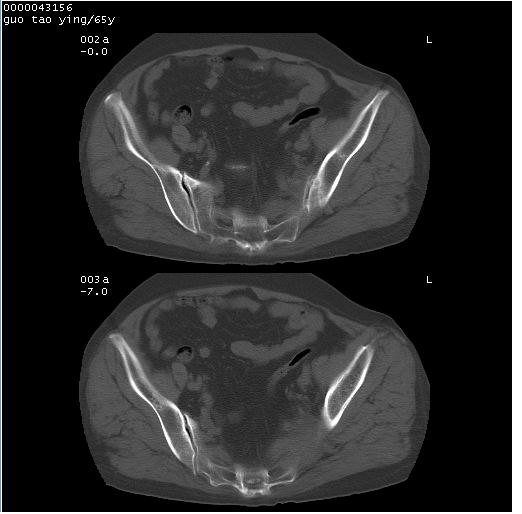

以下是引用黑白光影在2008-1-30 13:22:00的发言:[br]支持左耻骨骨折。[br]未见骶骨骨质明确破坏改变。[br]经楼主提示(勿局限于外伤)。考虑为右侧腹股沟直疝。[br][br][br][br]